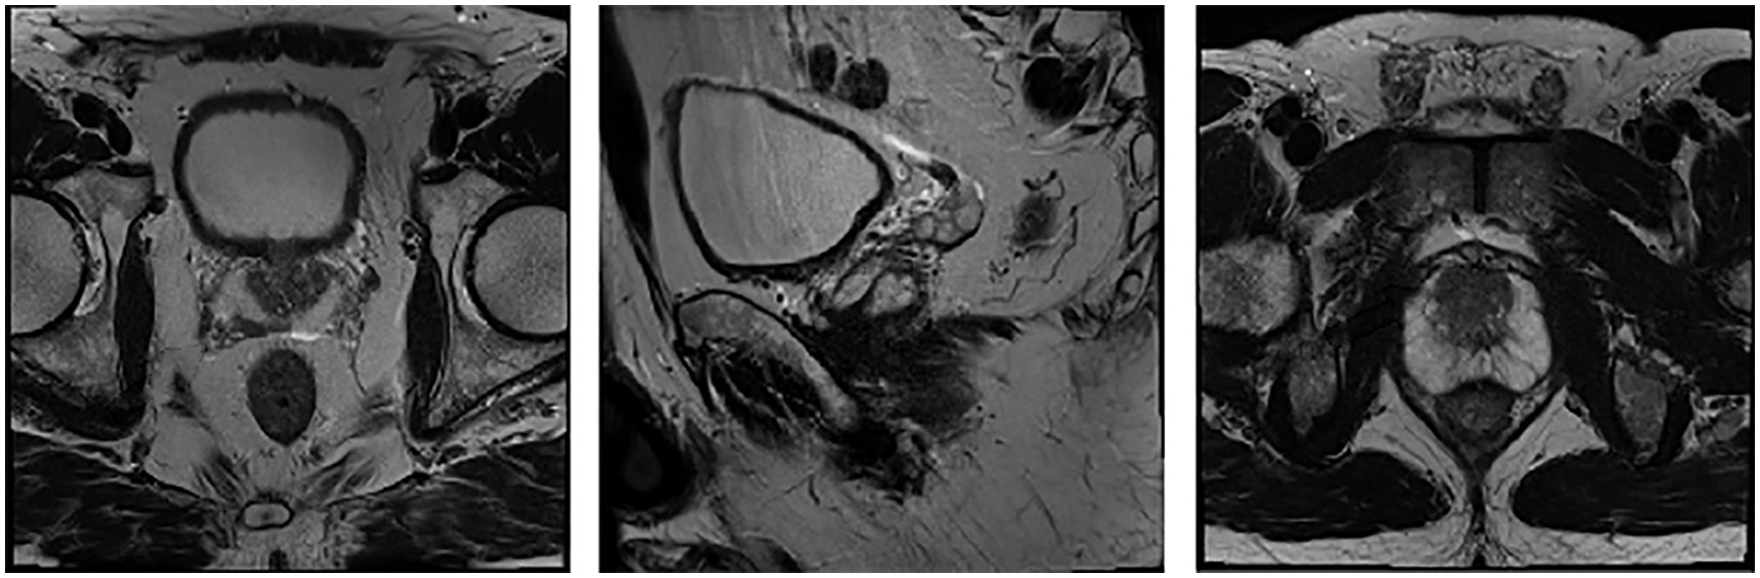

The performance validation of the DTL-PSCC technique takes place using the PROSTATEx-2 Challenge dataset [22], which holds a set of 162 MRI images with 5 class labels namely transaxial T2W, sagittal T2W, ADC, DW, and Ktrans. In this study, the five classes are represented by targets. The results are examined under varying ratios of training and testing data. A few sample images are demonstrated in Fig. 3.

Figure 3: Sample images